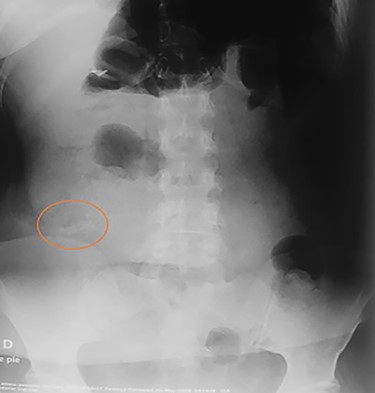

On clinical examination, a dehydrated and tachycardic (112 bpm) patient was encountered, she had diffuse pain in her lower abdomen without tenderness. After reanimation, an abdominal X-ray found two metal bodies in the bowel (Fig. 1); therefore, a computed tomography (CT) was requested, which revealed two metal foreign bodies, (razor blades) one in the stomach and one in the cecum without pneumoperitoneum (Fig. 2). As the patient did not have any tenderness, an upper endoscopy and colonoscopy were planned. During the upper endoscopy, the razor blade was detected in the antrum and was embedded in the mucosa (Fig. 3). After several failed attempts to remove the foreign object, the procedure was interrupted due to a risk of inadvertent perforation, and surgery was decided.

Abdominal X-ray on the postoperative period without any razor blades.